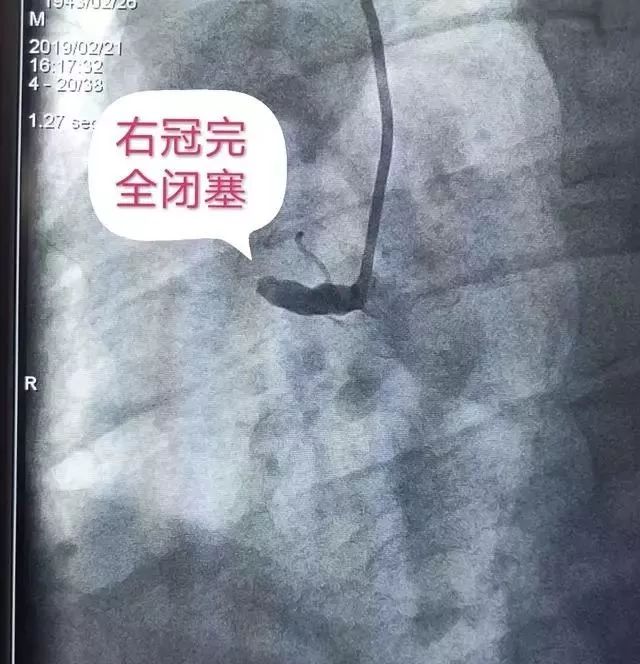

急诊科马上联系心内科,紧急植入临时起搏器,急诊行冠脉介入治疗:术中造影示右冠近段完全闭塞,前降支中段重度狭窄。开通右冠后反复室颤电复律5次(相当于心脏骤停5次),右冠近中段大量血栓,决定先用血栓抽吸导管抽吸血栓。